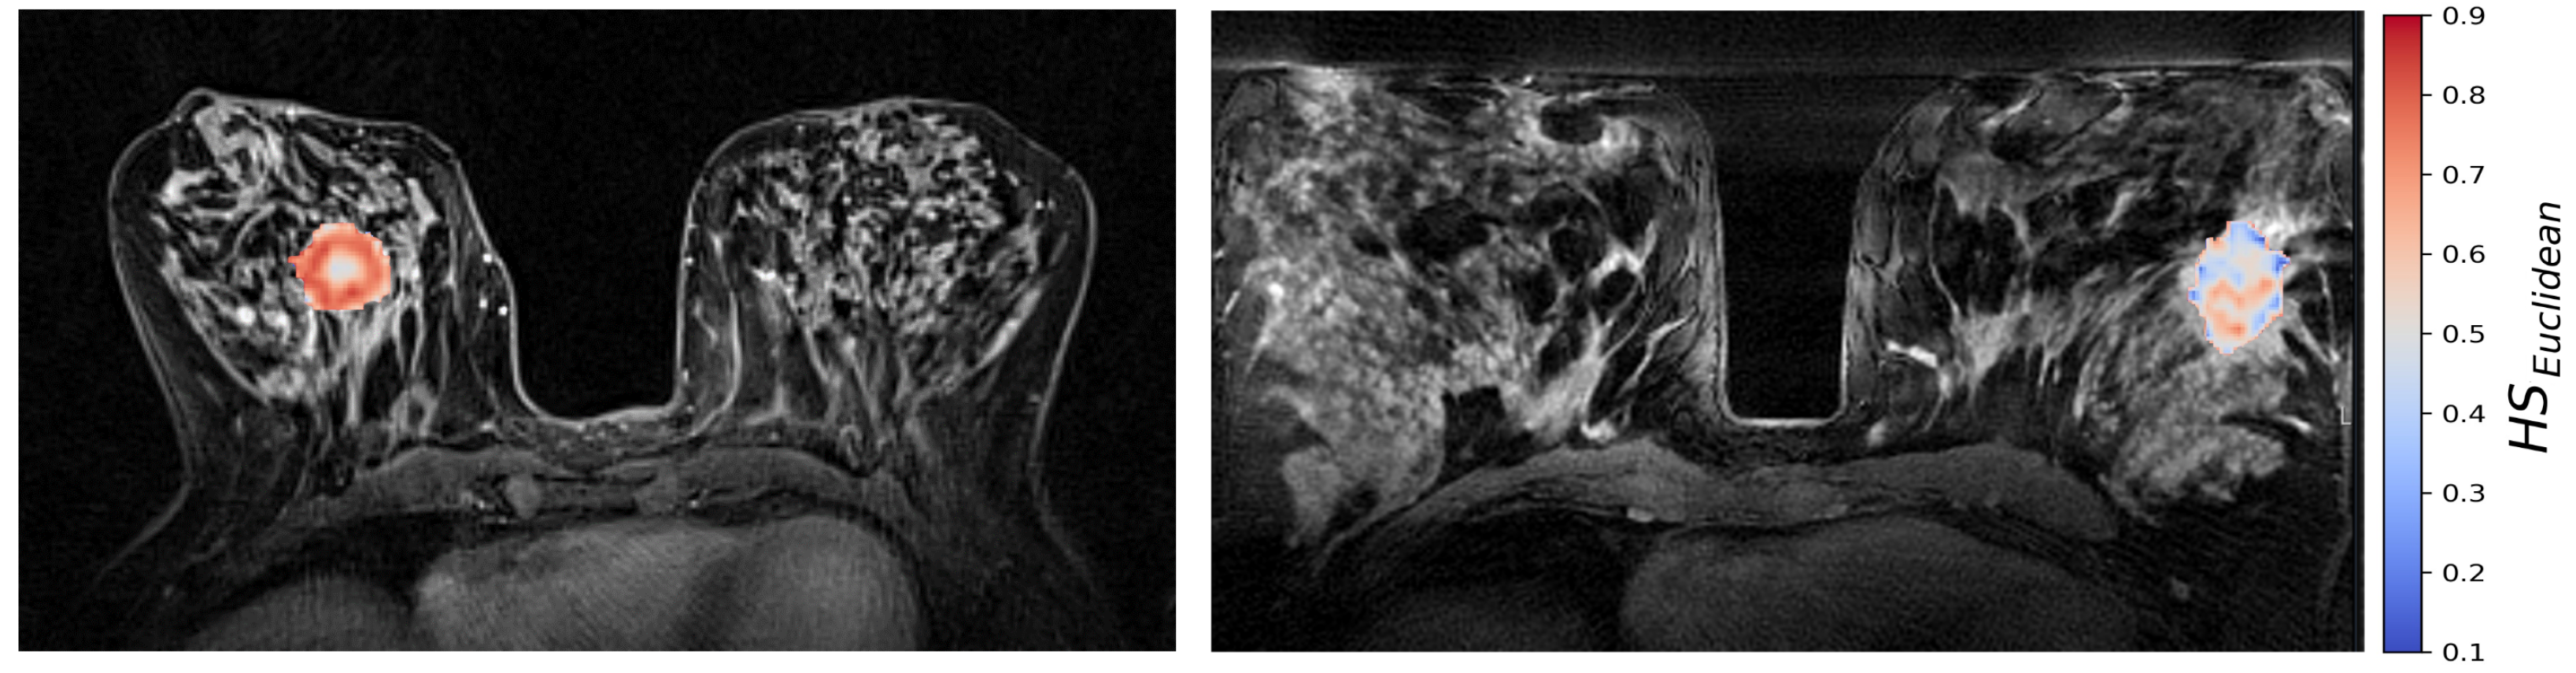

The generalized CSH method allows creation of continuous hypoxia maps of the whole tumor with the same spatial resolution as the DW MR images. Figure 5 shows the calculated hypoxia maps for two of the patients with low and high H S m o l , respectively.

Figure 5. CSH hypoxia maps of the same two patients as shown in Figure 2; one patient with a high molecular hypoxia score H S m o l = 0.33 (left), and one with a low molecular hypoxia score H S m o l = 0.23 (right).

Median H S E u c l i d 4 was significantly correlated to H S m o l (Spearman ρ = 0.31 , p < 0.01 ). In the binary hypoxia categories, median H S E u c l i d was significantly higher in the more hypoxic tumors(median H S E u c l i d = 0.39 ) than in the less hypoxic tumors (median H S E u c l i d = 0.33 ), p = 0.001 . This significance level was similar to the level obtained from the optimal linear decision boundary identified in Figure 4. Figure 6 shows how the three different methods of identifying tumor hypoxia using the CSH-concept compare.